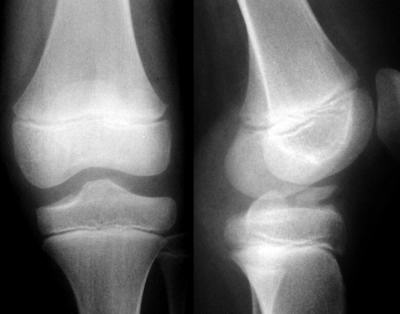

İki yönlü diz grafileri tanı için genellikle yeterli olur. Tünel grafisi kırığı daha iyi demonstre edebilir. Kırık parçanın büyük kısmı kıkırdak olduğu için, direkt grafilerde sadece ince kabuk şeklinde bir parça halinde gözlenebilir, bu parçanın gerçek boyutu konusunda yanıltıcı olabilir. Eşlik eden yumuşak doku lezyonları konusunda şüphe var ise MRG ile değerlendirme uygun olur.Sınıflama